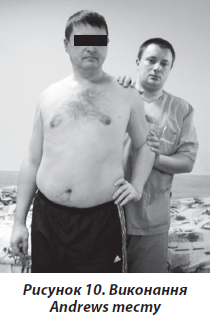

Для виконання Andrews тесту пацієнт розташовував хвору руку на поясі. Лікар ставав за спиною пацієнта та проводив компресійне зусилля долонею, розташованою на задній поверхні ліктьового суглоба по вісі плечової кістки (рис. 10). Тест вважався позитивним при виникненні болю в плечовому суглобі.